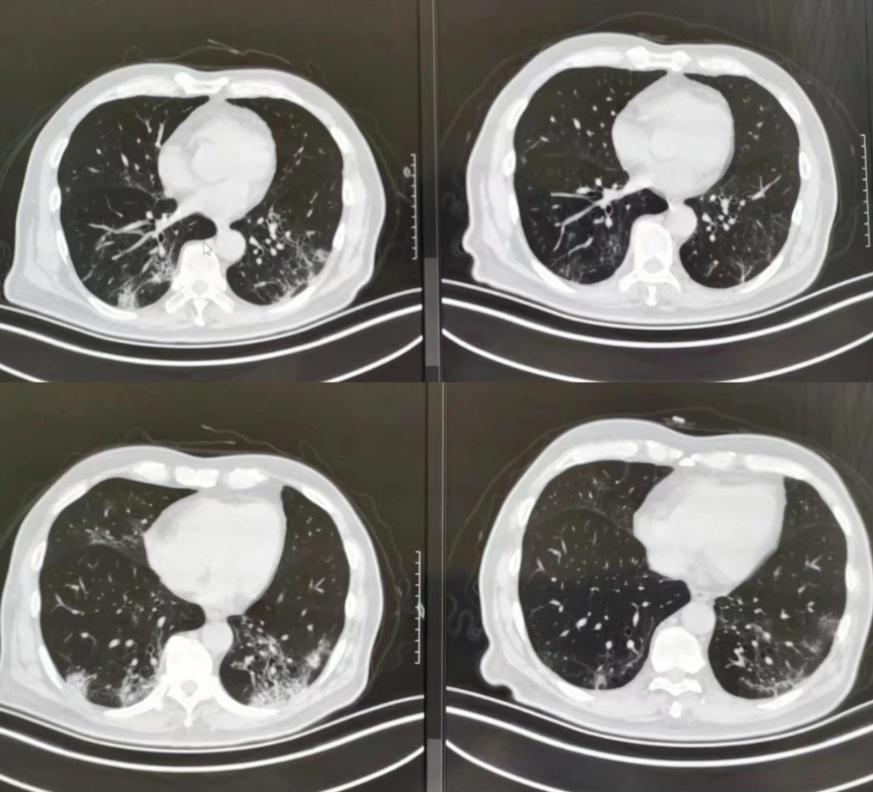

74岁的李老伯有30多年的吸烟史,既往有轻度的肺气肿,去年12月下旬感染新冠病毒后,他的两肺多发炎症,收入了上海市胸科医院的呼吸与危重症医学科病房。老伯“阳康”出院后于近日来医院复查,却发现了自己肺部出现了肺间质改变。

市民李先生“阳康”后查出了“磨玻璃小结节”。李锋表示,刚刚感染好就去查胸部CT,可能会发现有些磨玻璃影、磨玻璃小结节,而这些都是因为感染之后出现的,一般不会再扩大,过一段时间就会慢慢康复了。他建议这类患者观察随访,3-6个月后复查CT即可。同时他也提醒,如果没有特别不舒服,胸部CT至少在“阳康”后3至6个月再进行。

症状轻的患者仅仅是出现了肺间质性炎症(或肺间质异常),算不上肺纤维化。李锋介绍,感染后肺纤维化患者多数是新冠重症、危重症患者,曾经出现过白肺。

对于这类感染相关肺纤维化患者,又分为两种情况,一种是感染后的间质性肺炎(或肺间质异常),可以不需要额外治疗,也可以采用抗氧化治疗,3至6个月后基本就会慢慢吸收好转。另一种是感染后的肺纤维化,也不需要过分担心,采用抗炎、抗氧化的治疗,特别严重的采用抗纤维化药物来治疗,多数在3至12个月也会慢慢好转。